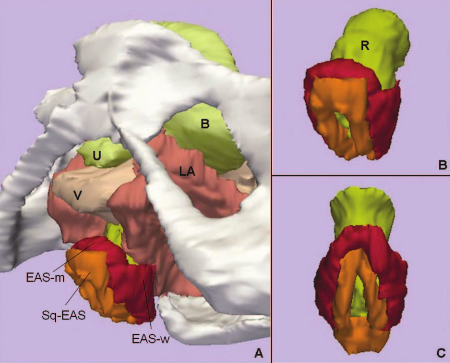

Magnetic Resonance Imaging and 3-Dimensional Analysis of External Anal Sphincter Anatomy

Publication: Obstet Gynecol. 2005 Dec;106(6):1259-65. PDF

Authors: Hsu Y, Fenner DE, Weadock WJ, DeLancey JO

Institution: Pelvic Floor Research Group, Division of Gynecology, Department of Obstetrics and Gynecology, University of Michigan, Ann Arbor, Michigan 48109-0276, USA.

Background/Purpose: To use magnetic resonance images of living women and 3-dimensional modeling software to identify the component parts and characteristic features of the external anal sphincter (EAS) that have visible separation or varying origins and insertions. METHODS: Detailed structural analysis of anal sphincter anatomy was performed on 3 pelvic magnetic resonance imaging (MRI) data sets selected for image clarity from ongoing studies involving nulliparous women. The relationships of anal sphincter structures seen in axial, sagittal, and coronal planes were examined using the 3D Slicer 2.1b1 software program. The following were requirements for sphincter elements to be considered separate: 1) a clear and consistently visible separation or 2) a different origin or insertion. The characteristic features identified in this way were then evaluated in images from an additional 50 nulliparas for the frequency of feature visibility. RESULTS: There were 3 components of the EAS that met criteria as being "separate" structures. The main body (EAS-M) is separated from the subcutaneous external anal sphincter (SQ-EAS) by a clear division that could be observed in all (100%) of the MRI scans reviewed. The wing-shaped end (EAS-W) has fibers that do not cross the midline ventrally, but have lateral origins near the ischiopubic ramus. This EAS-W component was visible in 76% of the nulliparas reviewed. CONCLUSION: Three distinct external anal sphincter components can be identified by MRI in the majority of nulliparous women.